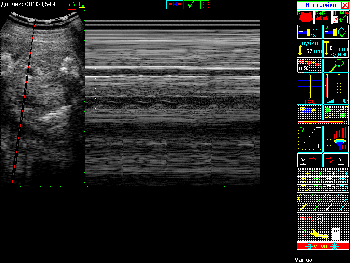

| Характеристики М-режима | Регулируемая скорость М-сканирования в режимах М и В+М (200, 100, 50 линий/сек). Выбор расположения М-строки. |

Примеры того, как выглядит экран при различных режимах сканирования можно увидеть в Таблице 4.

Таблица 4. Общий вид экрана в различных режимах сканирования.

| Вид экрана | Режим сканирования |

|---|---|

![]() |

Режим В+М |